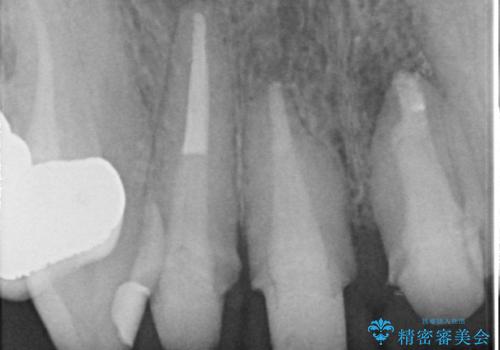

- 前歯の長さが違うのが気になるといらっしゃった方の症例です。

根尖病変を認めたため再根管治療を行った後、オールセラミッククラウン(スペシャル)にて補綴を行いました。

歯肉の腫れをより改善するため歯周外科を提案しましたが希望されませんでした。